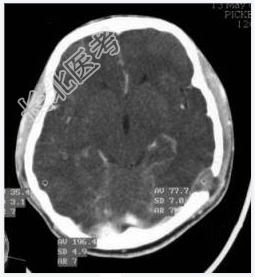

- [材料题] 病历摘要:男性,20岁。

主诉:发现头皮软组织肿物3个月。

现病史:三月前发现左枕部软组织轻微突起伴隐痛,到当地医院检查发现左枕部颅骨骨质缺损,未作具体治疗,现觉头皮肿物增大,时伴有气促、头痛。

专科检查:左颞枕部软组织略膨起,较软,各项病理反射(-)。